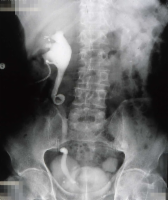

Als Komplikation ausgedehnter Mündungsdivertikel kommt es zu Abflussbehinderungen mit entsprechender Beeinträchtigung der Nierenfunktion. Als Beispiel die Harnstauungsniere bei einem Erwachsenen mit Abflussbehinderung durch ein ausgedehntes Mündungsdivertikel. Zunächst Harnableitung, dann Divertikelabtragung und Reimplantation (Abbildung HG1).

c